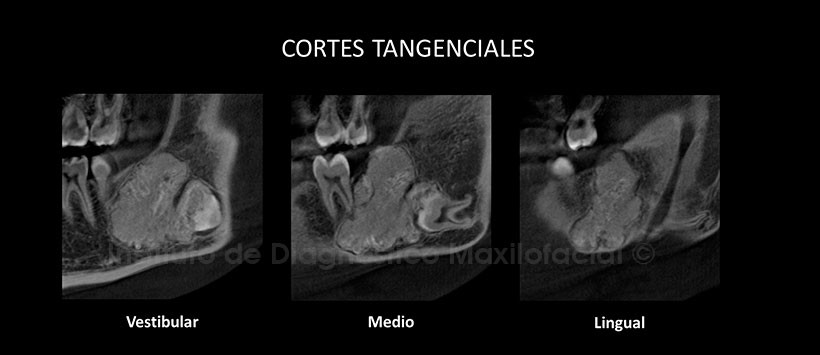

En los cortes axiales de maxilar inferior, pudimos observar el aumento de tamaño de la tabla ósea lingual y vestibular, siendo esta ultima la de mayor predominio (Figura 2). Así mismo en los cortes transaxiales y tangenciales podemos observar la estrecha relación de esta lesión con los ápices de la pieza 37, también se aprecia el adelgazamiento de a cortical lingual a causa de esta lesión y el desplazamiento hacia caudal del conducto dentario inferior. (Figura 3 y Figura 4)